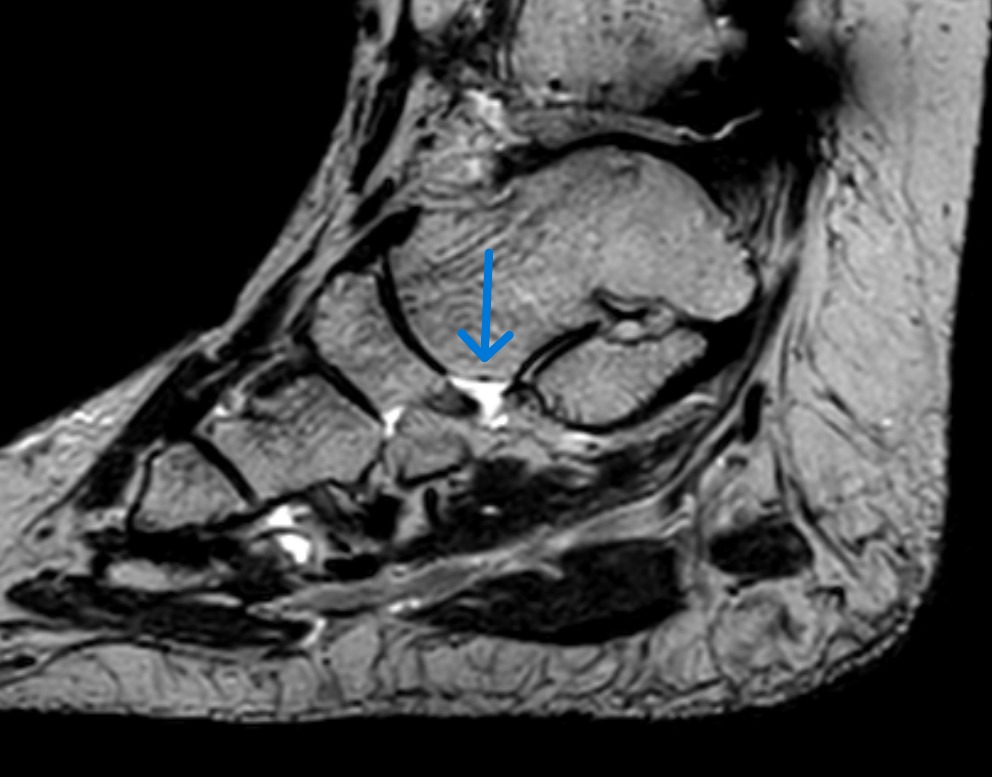

posttraumatische Läsion Pfannenband Ligamentum talo-naviculare plantare

posttraumatische Läsion Pfannenband Ligamentum talo naviculare plantare